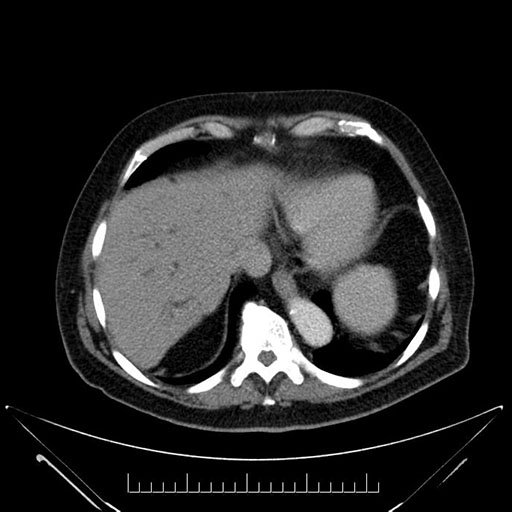

Axial - stented